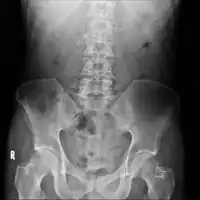

The diagnosis of chronic pancreatitis is based on tests on pancreatic structure and function. Serum amylase and lipase may be moderately elevated in cases of chronic pancreatitis. A secretin stimulation test is considered the best test for diagnosis of chronic pancreatitis. Other tests used to determine chronic pancreatitis are serum trypsinogen, computed tomography, ultrasound and biopsy.[9][10]

On CT scan, pancreatic and bile duct dilatation, atropy of pancreas, multiple calcifications of the pancreas, and enlargement of pancreatic glands can be found.[12]